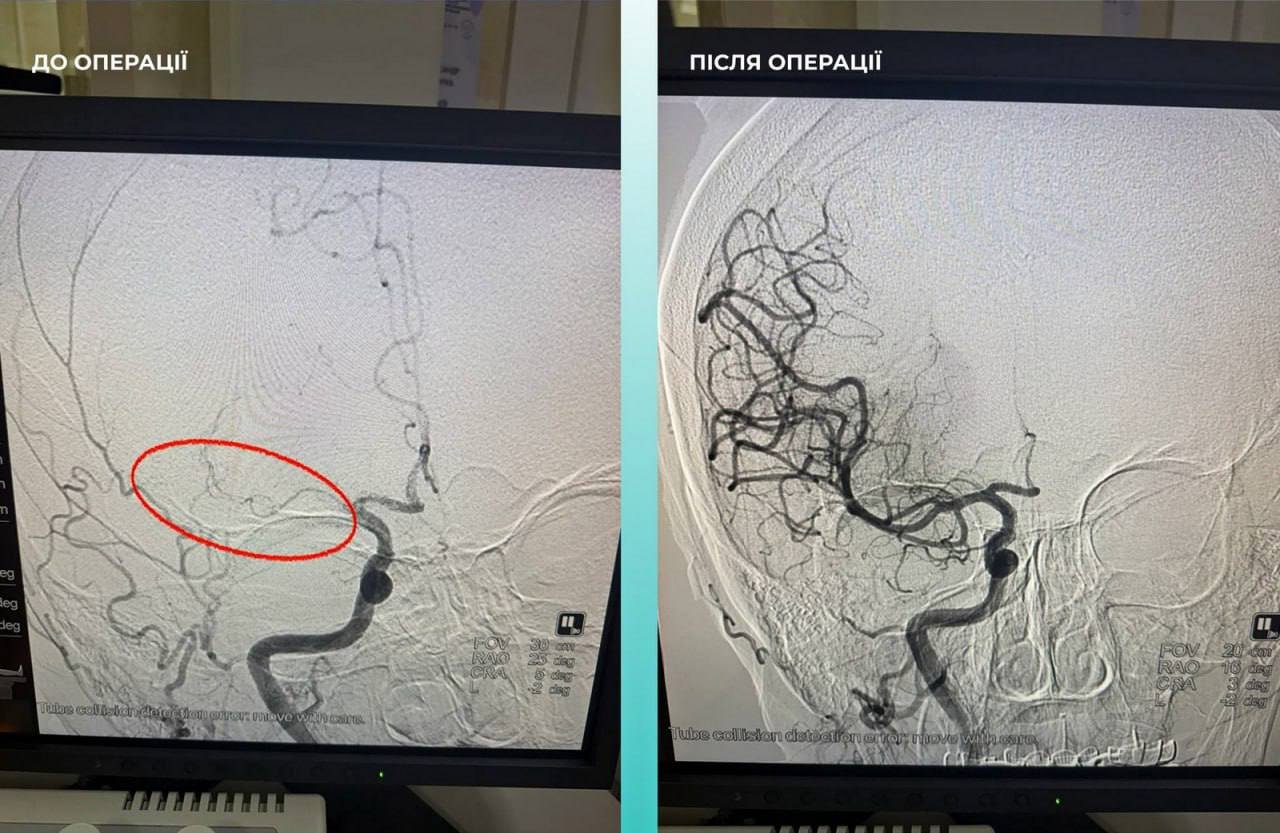

У пресслужбі Одеської міської ради повідомили, що до медзакладу одеситку доставили у важкому стані. Під час комп’ютерної томографії лікарі виявили закриття середньої мозкової артерії, що підтвердило діагноз гострого інсульту.

Мультидисциплінарна команда лікарів ухвалила критично важливе рішення — провести одночасну тромбектомію з мозкової та легеневої артерій. Наразі стан пацієнтки суттєво покращився, вона перебуває під наглядом медиків та продовжує відновлення.